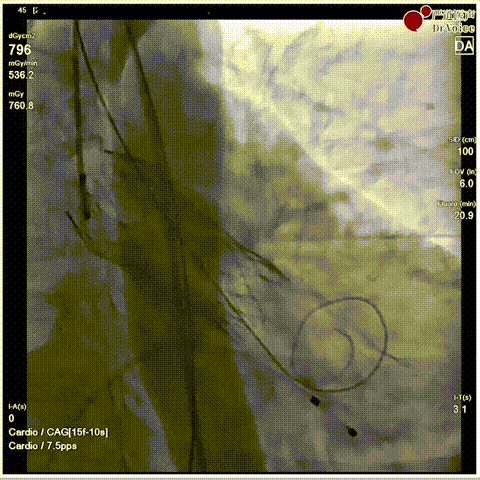

手术瓣膜释放后造影(4例)

病例一

病例二

病例三

病例四

快速过弓跨瓣(4例)